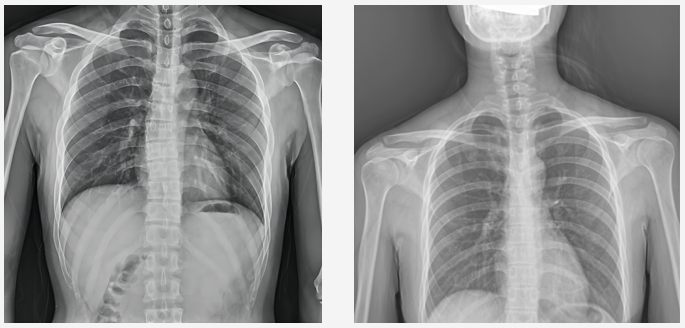

普爱动态DR临床图像

DR图像质量对比图

当前国产DR都尤其重视图像后处理系统的升级,如普爱医疗研发生产的多功能动态DR(型号:PLX8100),应用了公司自主研发的组织均衡技术,它是基于低灰度区扩展到高灰度区间的多层分级细节均衡算法。对于人体图像,通过组织均衡后,图像细节突出明显,肺纹理末端细小血管及骨骼的纹理、肌肉层次等均可清晰显示。